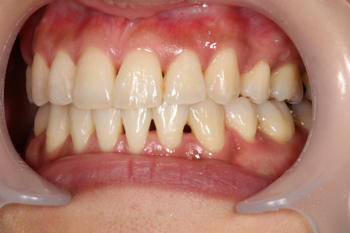

叢生と上顎前突の方のマルチブラケットによる歯列矯正

歯並びが気になるということで矯正相談に来られた患者様です。当初別の医院で非抜歯矯正も検討されていたそうですが、治療計画・費用・期間を説明したところ、当院での抜歯矯正に踏み切られました。

Before

治療方法としては、抜歯を行った上での通常のマルチブラケット装置による矯正です。

約3年強で歯並びが整いました。歯並びが整うことにより、もともと叢生のあった方は特にブラッシングによる磨き残しが少なくなり、むし歯や歯周病になるリスクが軽減されます。